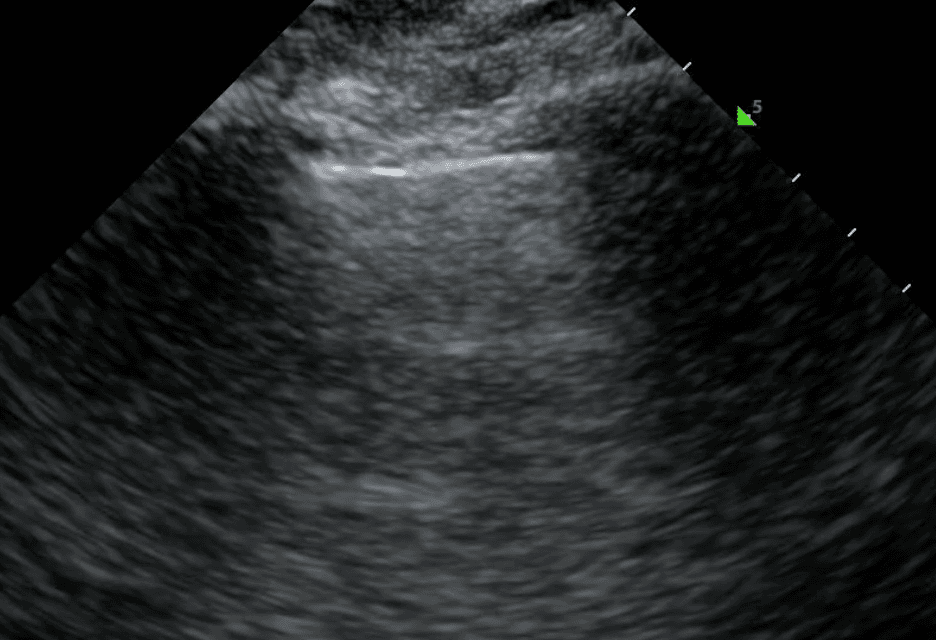

A normal pleural line is thin (less than 3 mm), smooth and continuous. In disease, the pleural line may be thickened or irregular. These characteristics can be combined with subpleural lesions and artifacts (such as A lines or B lines) to form a comprehensive differential diagnosis for lung pathology.

An irregular pleural line describes any disruption to the smooth, continuous appearance of the pleura. This can manifest as jaggedness, unevenness or fragmentation of the pleural line. Pleural thickening refers to a pleura that is thicker than 3mm. In the acute setting, an irregular or thickened pleural line points toward an infectious or inflammatory process such as pneumonia, acute respiratory distress syndrome (ARDS) or, less commonly, malignancy. For a more complete picture, pleural changes should be considered alongside other sonographic features including B lines, lung sliding and consolidation.